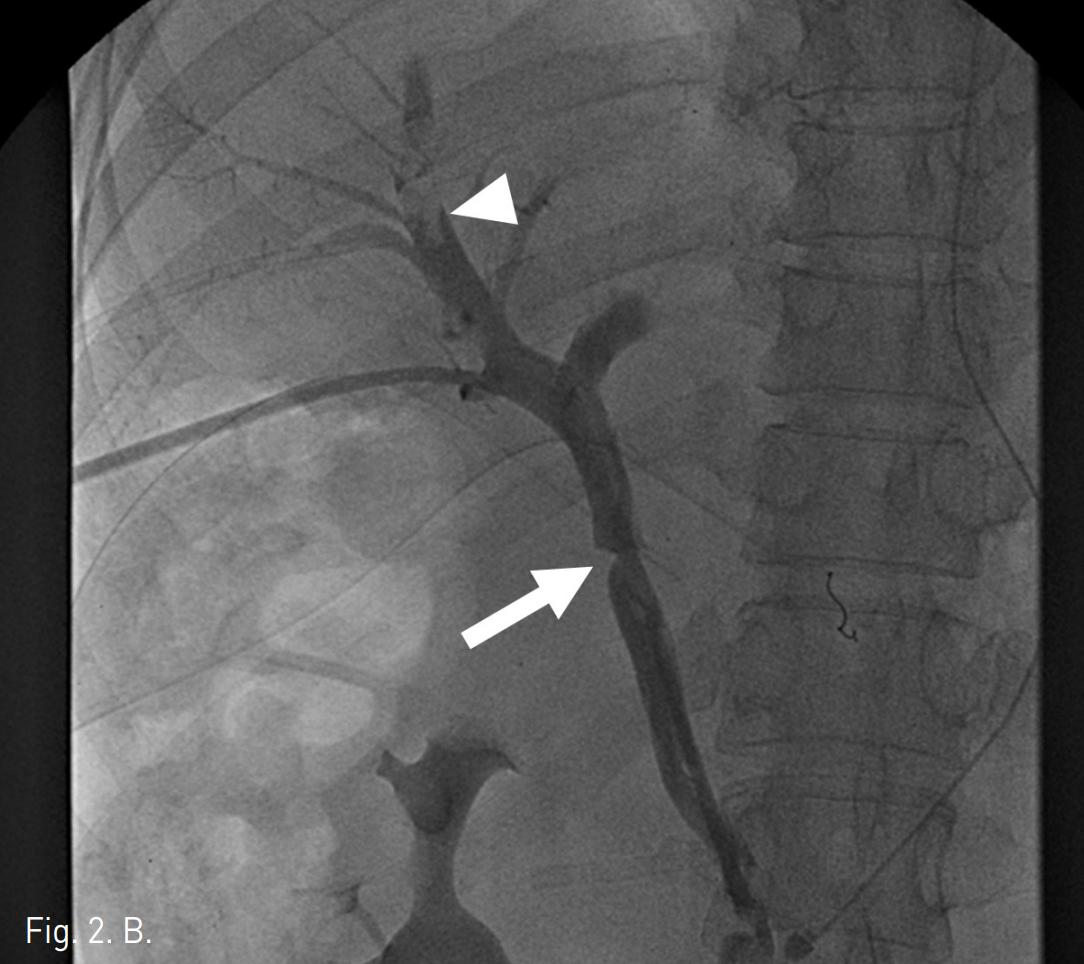

초음파 유도 하에서 우측 문맥을 20G Chiba needle을 이용해 직접 천자한 후 문맥 조영 영상에서 문맥부 합성혈관의 혈전성 폐색을 확인하였다(Fig. 2A). 5F Davis catheter (Cook, Bloomington, IN, USA)와 urokinase (200K unit)를 이용한 혈전용해술, 7F Sheath catheter (Cook, Bloomington, IN,USA)를 이용한 흡입 혈전제거술과 stent를 이용한 치료를 계획하였다. 혈전용해술 및 흡입 혈전제거술을 시행한 후 문맥의 혈류가 회복되었으나 이 과정에서 간 내 문맥(intrahepatic portal vein)에 혈전성 색전에 의한 것으로 보이는 간 내 문맥의 충만결손이 발생하였고(Fig. 2B), 이에 대해 다시 흡입혈전제거술을 시행하여 문맥의 흐름을 원활히 하였다. 이후 자가팽창형 스텐트(10mm x 80mm)(S&G biotech, Seoul, Korea)를 합성혈관의 근위부 및 원위부 접합부를 모두 포함하도록 설치하였다(Fig. 2C), 스텐트를 위치시킨 후 시행한 문맥조영술에서 간 내 문맥의 충만결손이 사라지고 스텐트 삽입 부위의 문맥의 혈류가 원활하며 출혈 등의 시술 후 부작용이 없음을 확인하고 시술을 종료하였다 (Fig. 2D).

B. Portal venogram after thrombolysis and aspiration thrombectomy shows a stenosis at the graft anastomosis (arrow). A filling defect suggesting embolic thrombus (arrowhead) is noted at the intrahepatic portal vein.